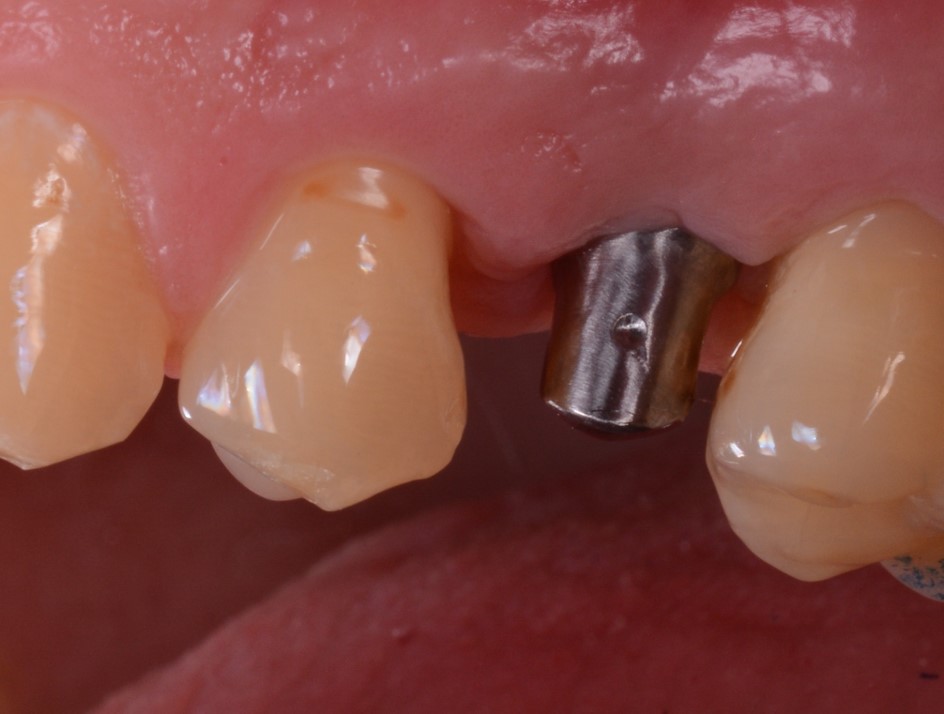

Il materiale prescelto per la stampa era un composito ibrido, caricato con ceramica, certificato per la stampa di restauri definitivi (Fig. 14). Il moncone individuale, fresato a 5 assi in titanio (TQM®, Gioia del Colle, Bari, Italia) veniva avvitato in bocca (Fig. 15,16) dopo rimozione della vite di guarigione; successivamente si applicava la corona definitiva (Fig. 17,18).

Inserimento del moncone individuale in titanio

Fig. 15. Inserimento del moncone individuale in titanio.

Scansione intraorale del moncone in posizione

Fig. 16. Scansione intraorale del moncone in posizione.